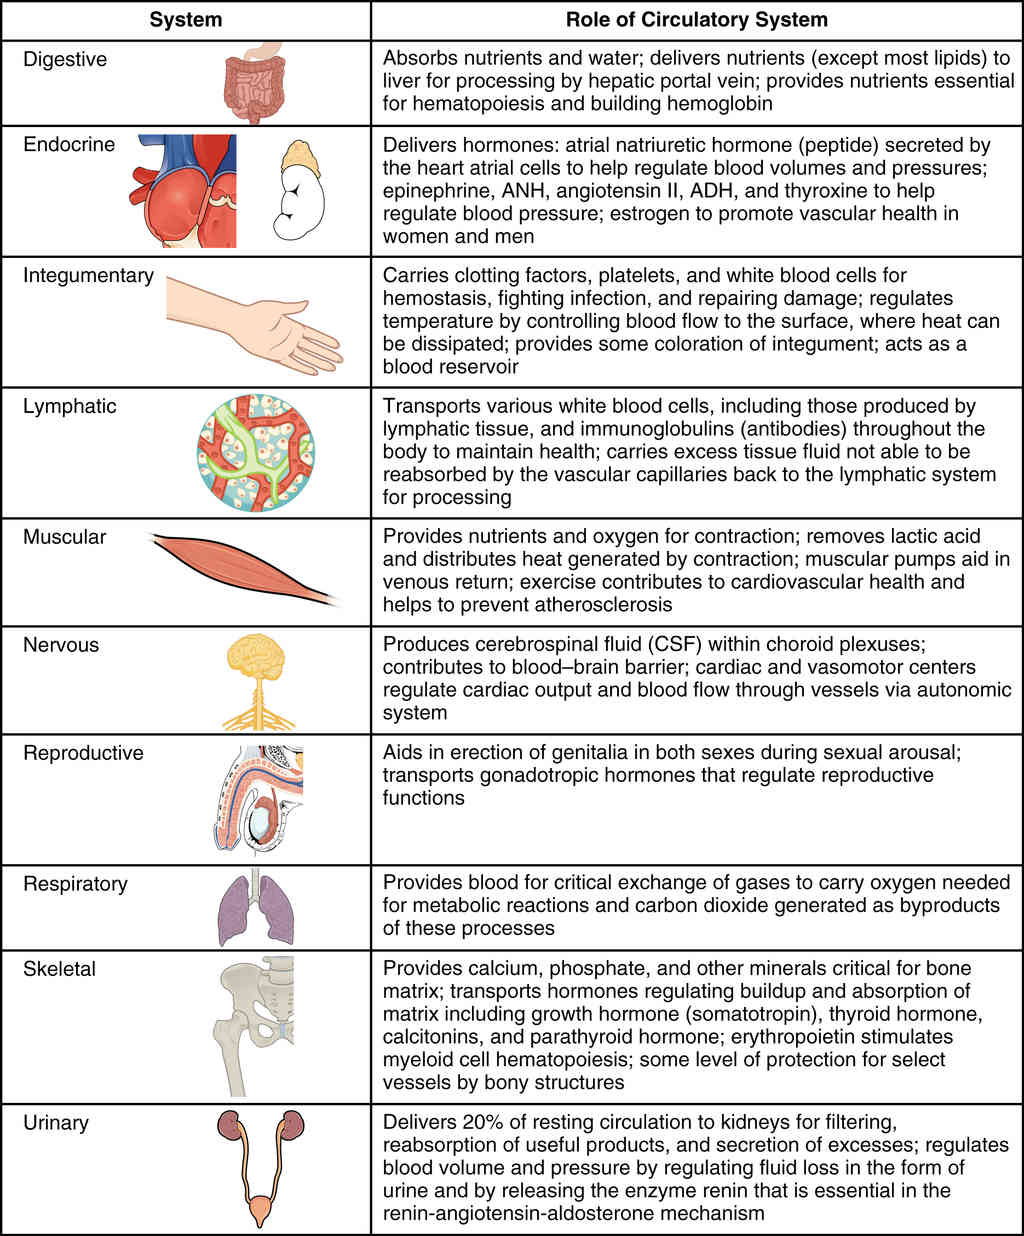

This page is under construction. For now, it is just a resource of the images found in the OpenStax Anatomy and Physiology Handbook. It wil slowly change into a revision tool. Each slide has a number. Use this to refer to the slide. When completed, it will have an unlabelled section, with labelled slides in parallel. On the unlabelled slides, write your answer and use the labelled slide to assess yourself. Keep track by also noting the number on each slide. Improvement at each attempt is important, more so than full marks on a first attempt.